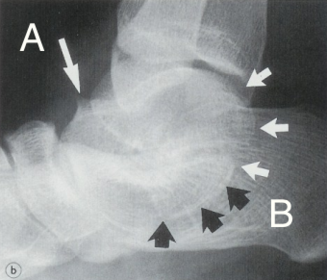

| What is this? What is shown by A and B? | STJ coalition A = talar neck spurring B = Halo or 'C' sign |